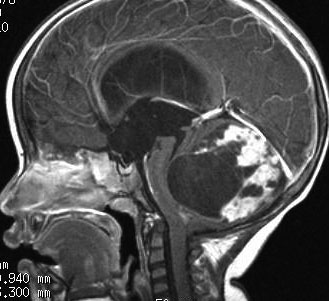

全く何もしなくても良い成人の毛様細胞性星細胞腫

20代女性に偶然発見された視床下部(第3脳室)腫瘍です,T1低信号,T2で高信号,右側のガドリニウム造影では全く増強されません。毛様細胞性星細胞腫と診断できます。眼科での視野検査で視野欠損はありませんでした。生検術もなにもせず経過をみました。

左が初診時,右が5年後のMRI画像です。腫瘍の大きさは全く同じです。このような腫瘍はしばしば経験します。慌てて生検術や開頭手術など計画しないで,画像診断をしっかりすることが大切です。